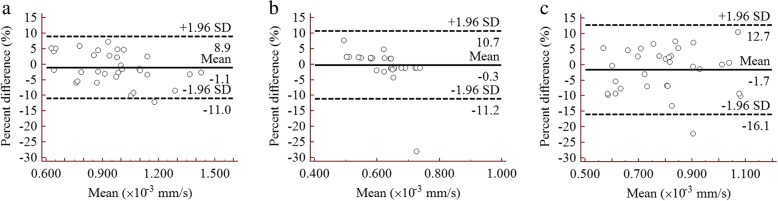

The statistical results of repeated ADC measurements are presented in Table 2. There was an excellent reproducibility for ADC values between two observers with ICC and CV values ranging from 0.920 to 0.998, and 1.475 to 5.568%, respectively. In addition, the mean percent difference between the paired measurements was relatively small, with a range of − 2.7 to 1.2%. Besides, narrow intervals were observed for those measurements using Bland-Altman plots in three represented b-value combinations (Fig. 2).

Fig. 2.

Bland-Altman plots show good agreement of the ADC measurements between two observers for three representative b-value combinations. a a b-value combination of 0, 1000 s/mm2. b a b-value combination of 100, 1000, 1500 s/mm2. c a b-value combination of 500, 1500, 2000 s/mm2